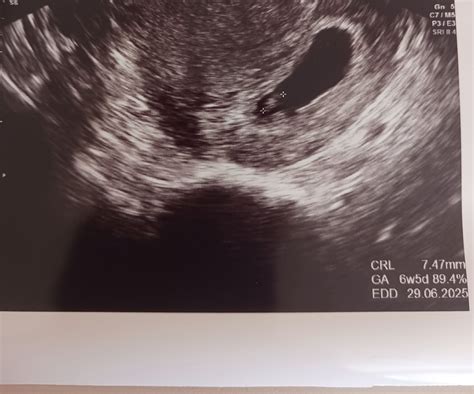

Pri ultrazvuku v tomto období lekár sleduje dĺžku plodu (CRL - crown-rump length), aby určil, či zodpovedá gestačnému veku. Meranie CRL v 10. až 13. týždni tehotenstva je najpresnejšie pre stanovenie termínu pôrodu.

- Šiesty týždeň tehotenstva: Toto obdobie je často považované za kľúčové pre prvú vizualizáciu embrya na ultrazvuku. Približne v polovici 6. týždňa tehotenstva je už spravidla viditeľné bijúce srdiečko, čo je dôležitý ukazovateľ životaschopnosti plodu. Embryo v tomto štádiu nadobúda typickejší ľudský vzhľad, začínajú sa vyvíjať základy končatín a začína pracovať placenta. Jeho dĺžka sa pohybuje okolo 4 mm. V tomto týždni sa uzatvára aj neurálna trubica, základ budúcej centrálnej nervovej sústavy.

- Srdcová aktivita: V 6. týždni tehotenstva je už väčšinou možné zaznamenať tlkot srdca embrya. Toto je pre mnohé ženy mimoriadne povzbudzujúci moment.

Vo všeobecnosti sa za zlomový týždeň pre vizualizáciu embrya a jeho srdcovej aktivity považuje 6. týždeň tehotenstva (počítané od poslednej menštruácie). Niektoré ženy môžu vidieť embryo a dokonca zaznamenať srdcovú činnosť už v 5. týždni, najmä pri použití transvaginálneho ultrazvuku. Ak plod v 6. týždni nie je viditeľný, neznamená to nutne problém. Môže to byť spôsobené neskorším uhniezdením embrya alebo inými faktormi. V takom prípade lekár zvyčajne odporučí kontrolné ultrazvukové vyšetrenie o týždeň neskôr.